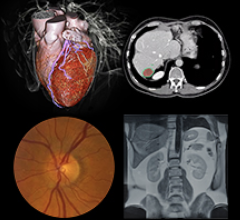

Radiology departments have many different needs and face a wide variety of challenges that can impact their departments ...

Bayer Radiology’s Barbara Ruhland and Thom Kinst discuss how radiology departments can address the many different ...